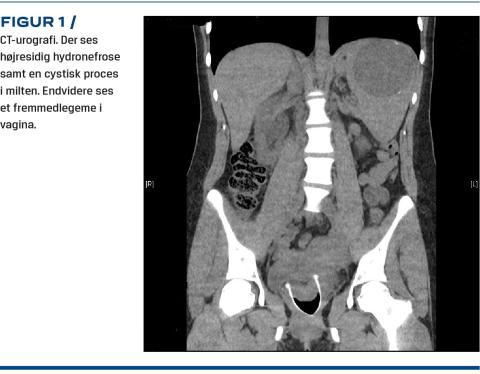

En måned senere henvendte hun sig igen med akkurat samme symptombillede, igen tydeligt smerteforpint, og atter var en urinstikstest positiv for blod. Udredningen blev suppleret med CT-urografi, og denne viste tegn på højresidig hydronefrose samt en cystisk proces i milten. Endelig viste urografien, at der i vagina sad et fremmedlegeme, der tydeligt pressede på højre urinleder (Figur 1). Fremmedlegemet viste sig at være en menstruationskop. Den blev fjernet omgående, hvorefter smerterne aftog kort tid efter. Patienten forblev indlagt til observation natten over og blev udskrevet i velbefindende i habituel tilstand dagen efter.

En kontrolskanning to uger efter viste fuldstændig regression af den tidligere sete højresidige hydronefrose. Patienten blev efterfølgende ambulant viderehenvist mhp. yderligere udredning af cysten.